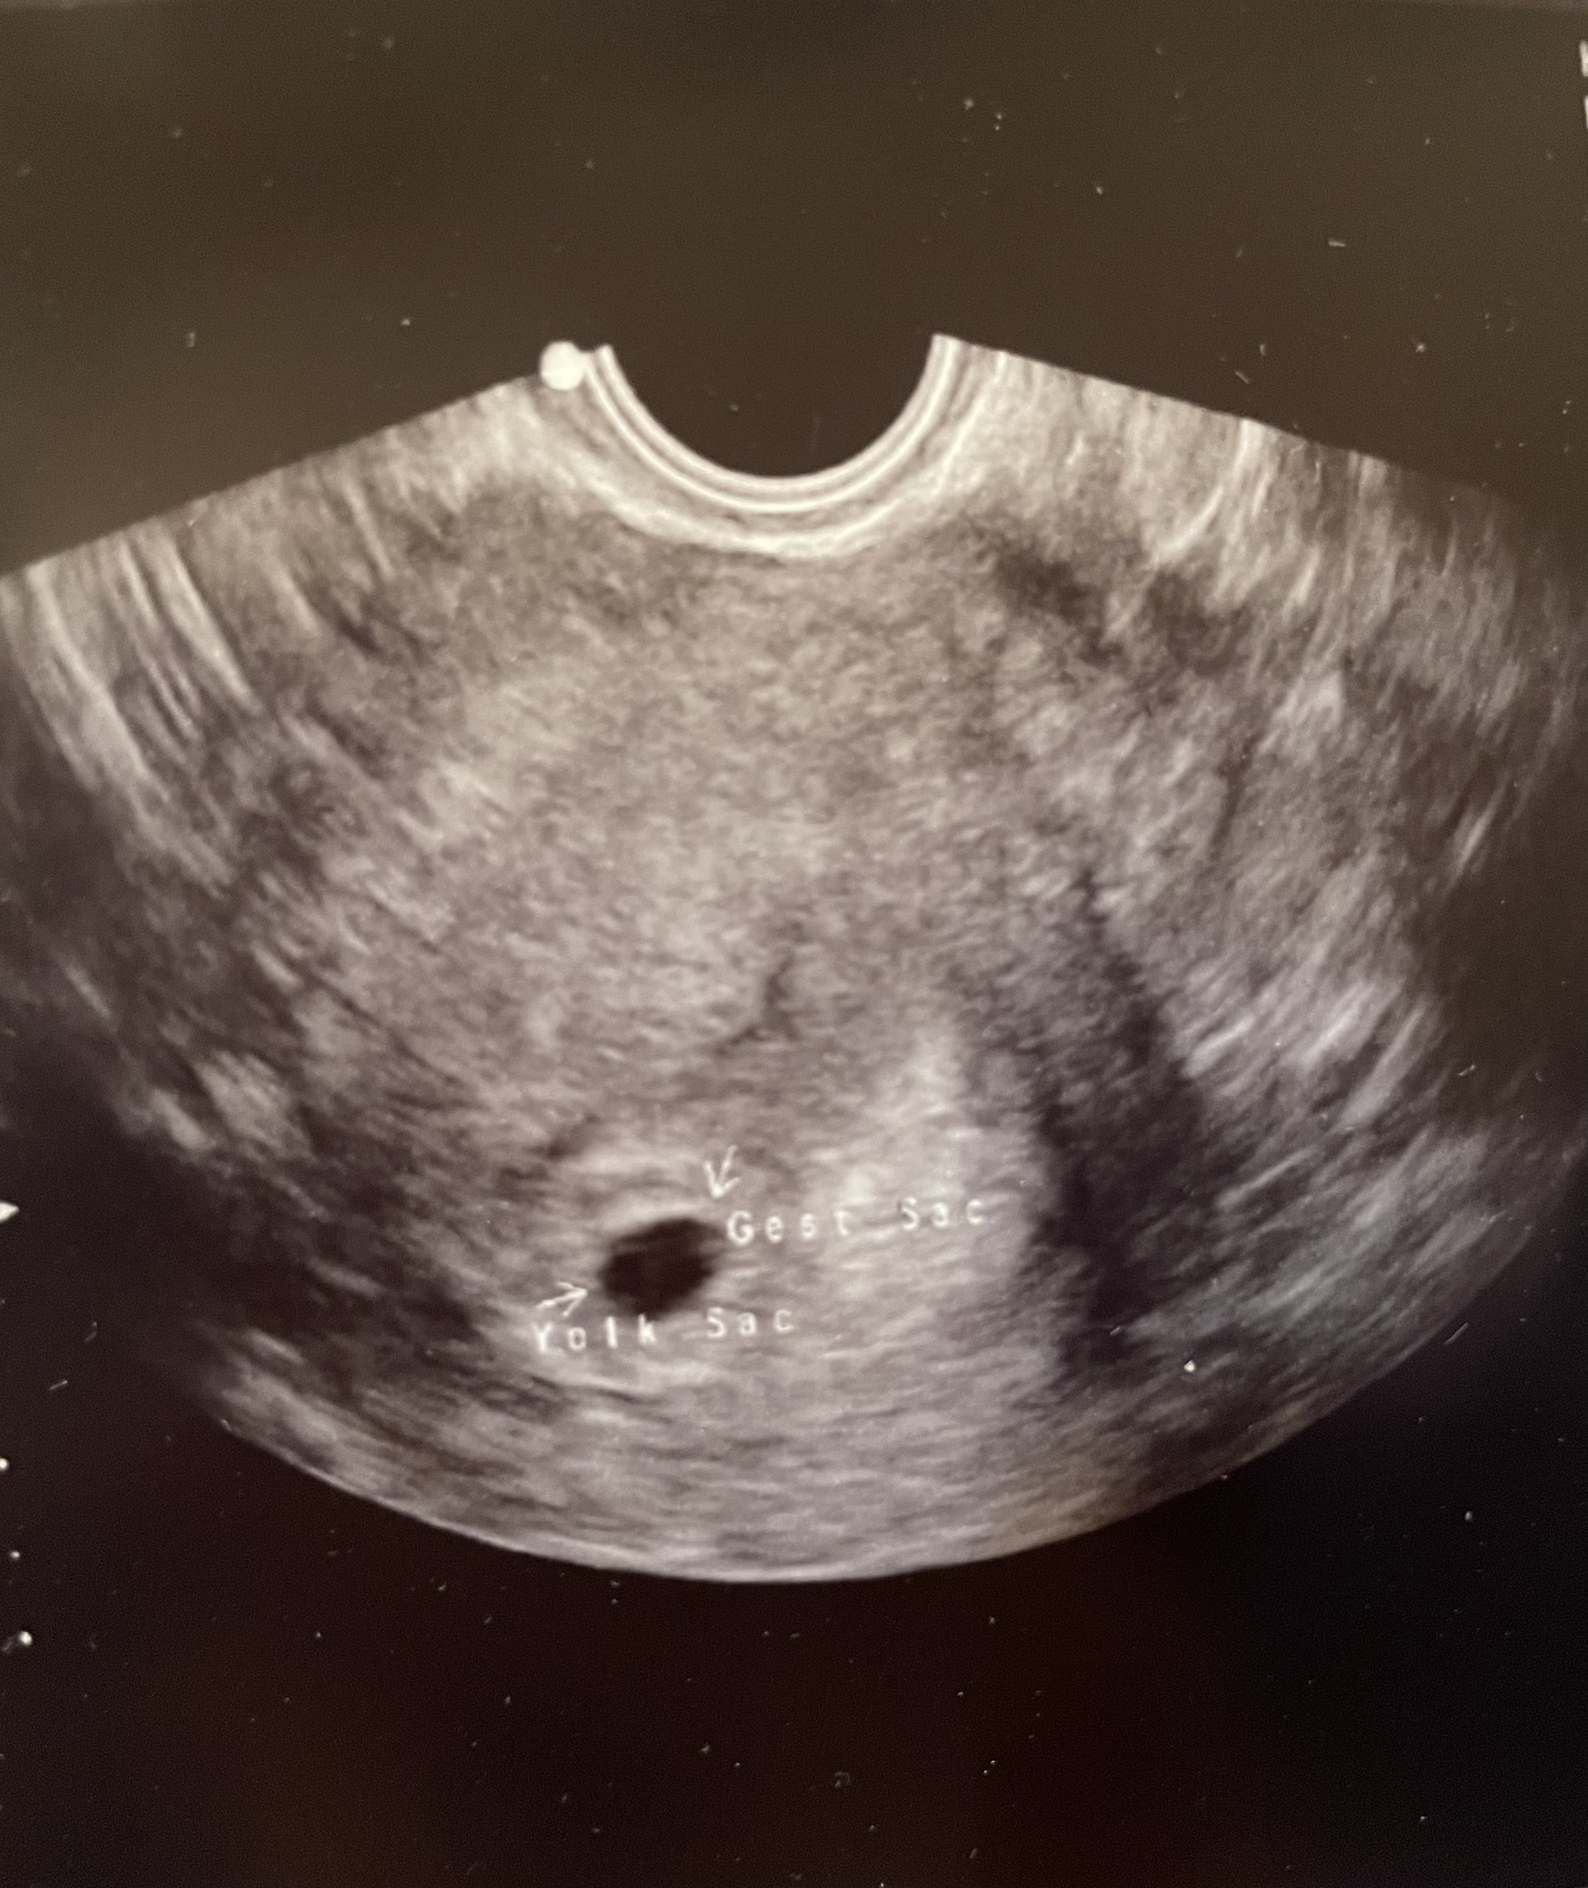

Fertility Treatments with risk of ectopic so I got my ultrasound early. Ended up being 6 weeks, 2 days and able to see the heartbeat at 115. Normal for the gestation since babes heart literally started beating 24-48 hours prior. Due Date August 6th!

After 5 losses, doc had me in at 6 weeks 1 day for early scan! First time seeing a heartbeat❤️ he said it looked great at 126 bpm! I have my 8 week scan in about a week and I cannot wait to see my lil bean again!